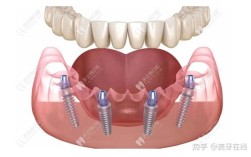

传统种牙需经历“拔牙-等待3-6个月-植骨-再等待3个月-戴牙”的漫长周期,而微创即刻种植技术通过“不翻瓣”或“小切口”手术,结合数字化导板,实现“即拔即种”——在拔除患牙的同时植入种植体,甚至当天安装临时牙冠,实现“当天种牙、当天用牙”。

该技术的核心在于“微创”与“即刻”:微创手术通过牙龈微小切口(约3-5毫米)植入种植体,不翻开牙龈瓣,减少对软组织的损伤,术后疼痛感轻、恢复快;即刻种植则依托数字化精准定位,确保种植体初期稳定性(骨量需充足),结合生物活性材料(如PRF富血小板纤维蛋白),促进拔牙窝与种植体周围骨组织同步再生,即刻种植对患者的骨量、牙槽骨密度及全身健康状况要求较高,需医生严格评估适应症。